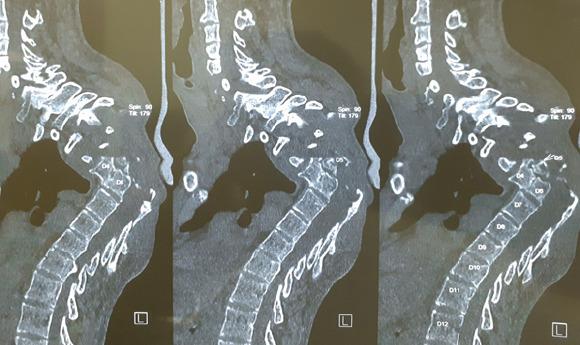

We present a case of 22-year-old male with NF-1 who came to us with gradually progressive upper back deformity and signs of early myelopathy for 2-3 months. The patient had a 100° proximal thoracic kyphosis and 100° scoliosis with no neurological deficit and brisk reflexes. A single stage posterior fixation with three column osteotomy at the apex of the curve was performed.

The kyphosis was corrected to 65° from 100, the scoliosis was corrected to 60° from 100. Clinically, the hump in the upper back was visibly reduced. At 1-year follow-up, the patient remained asymptomatic with no loss of correction and implant breakage on X-ray.